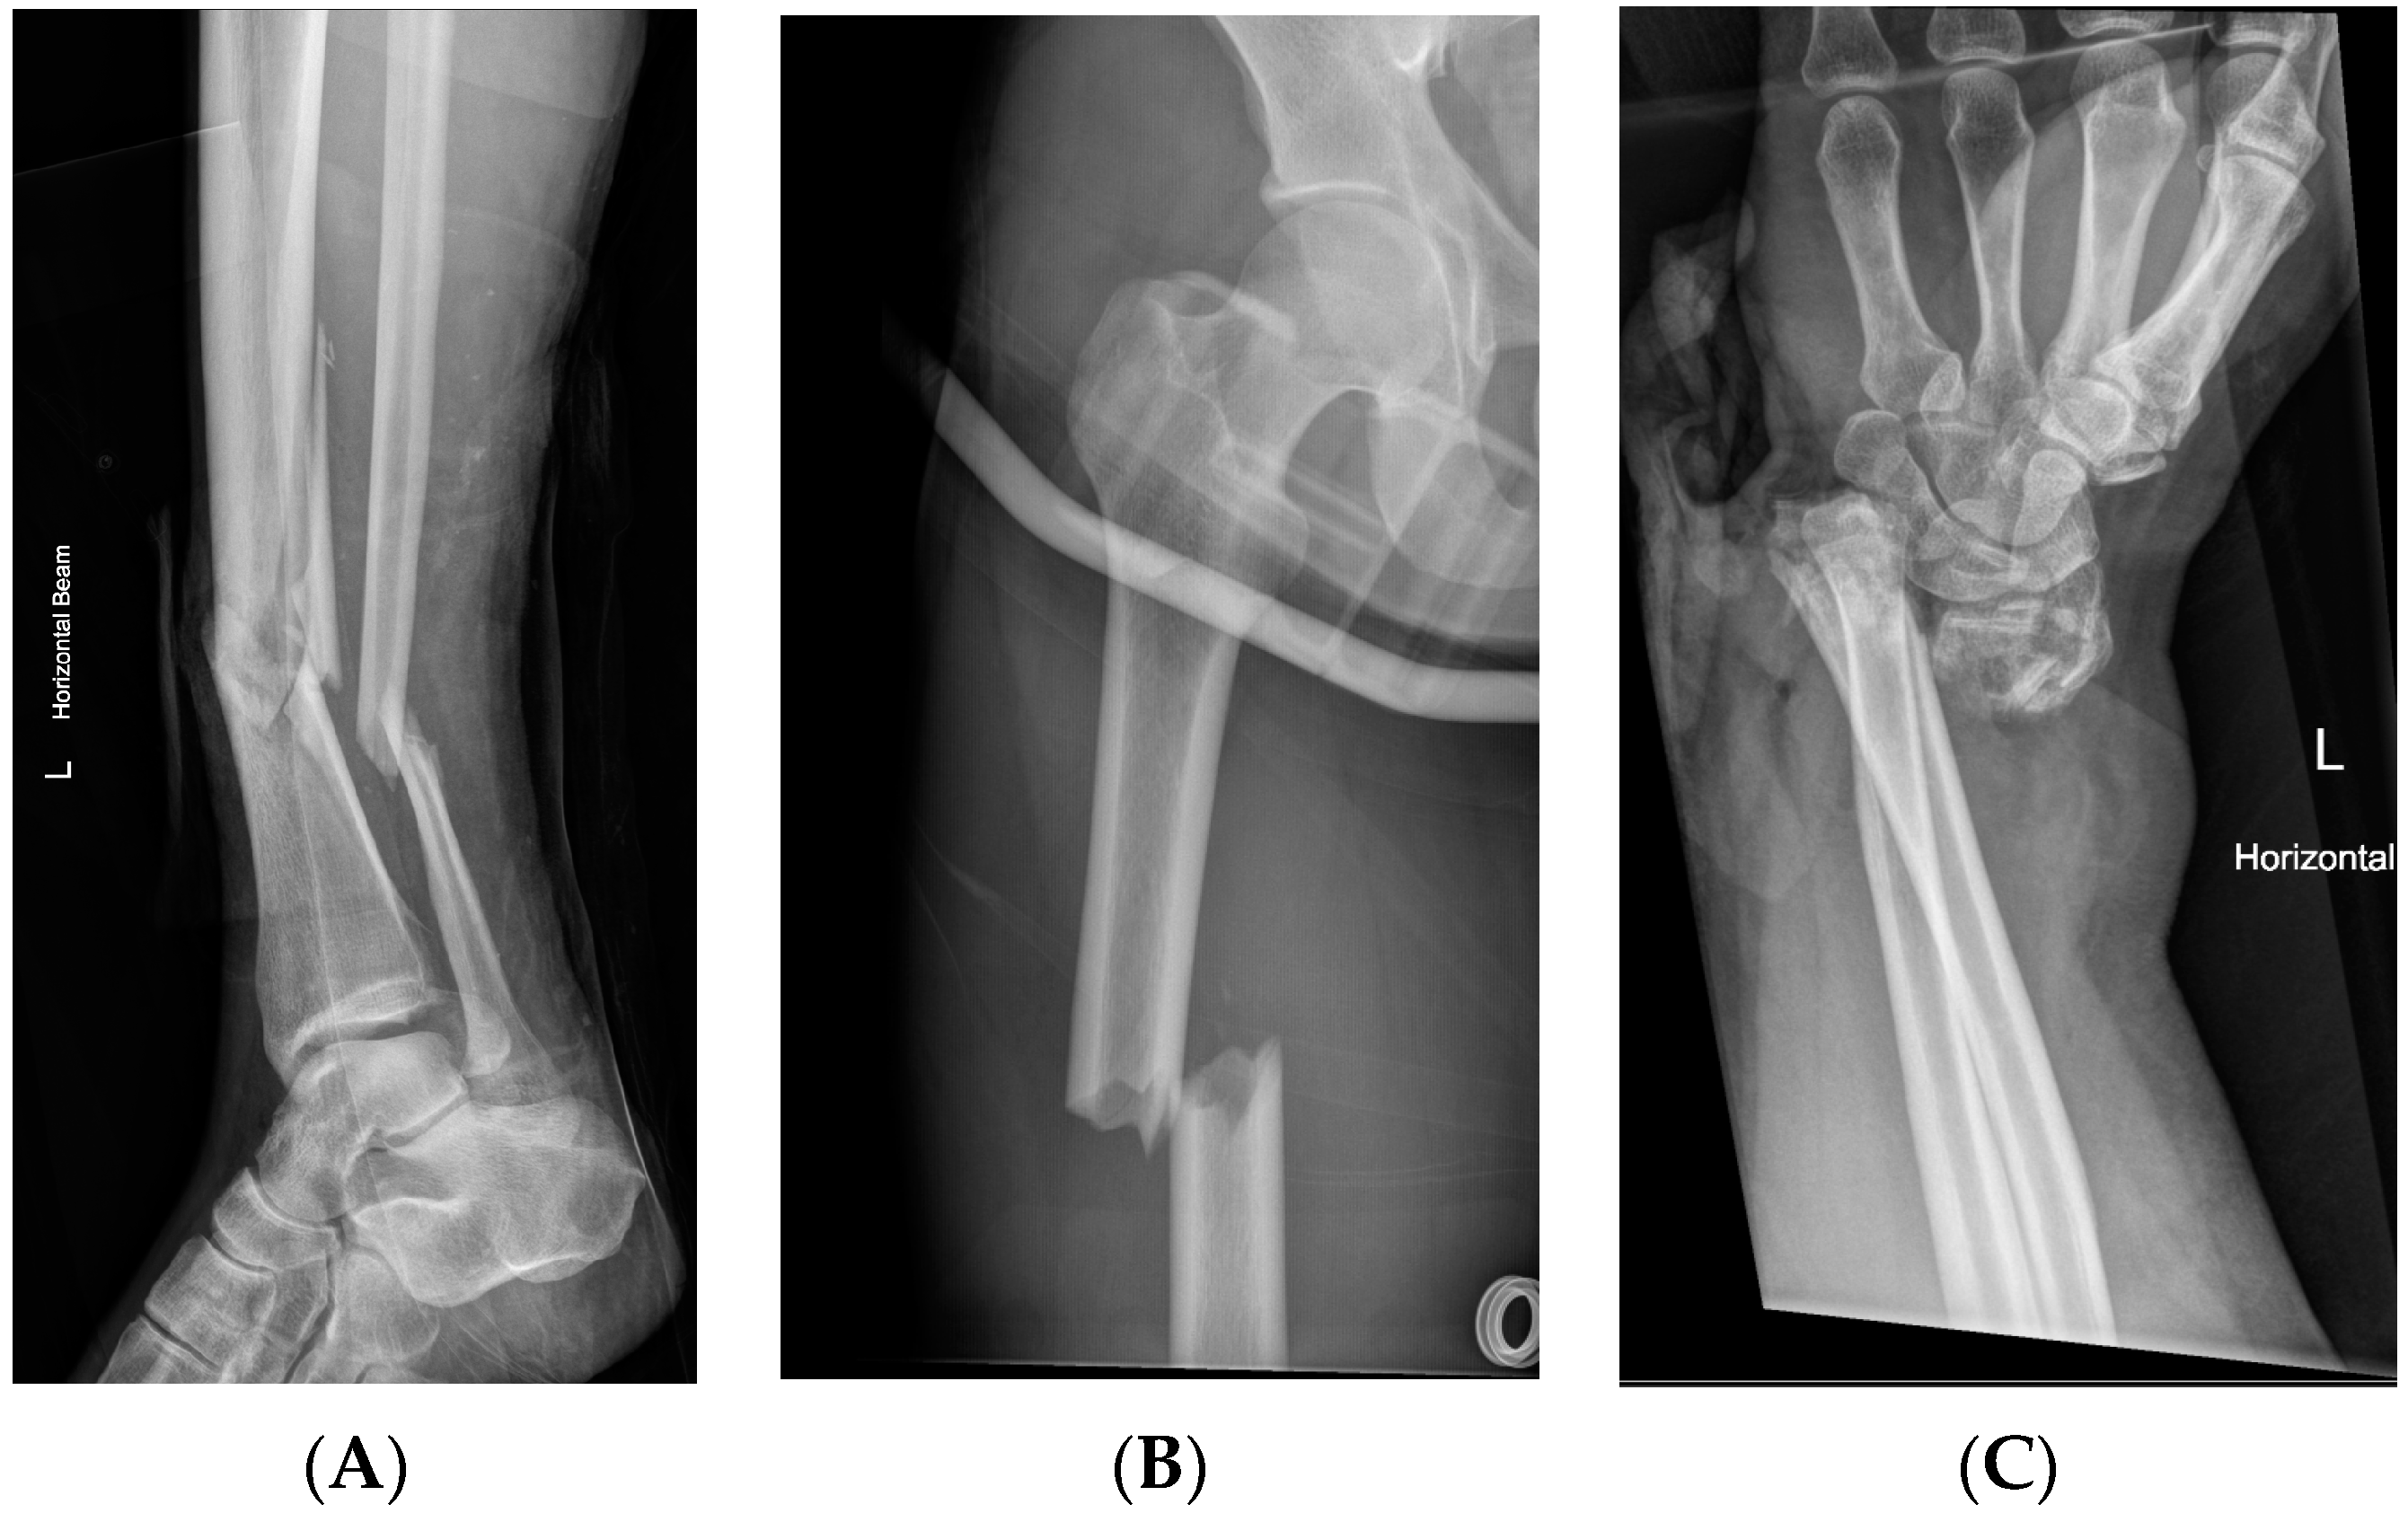

| Upper Limb Injuries | 33 | ||

| Humerus | 4 | 1 | 3 |

| Radius | 20 | 3 | 17 |